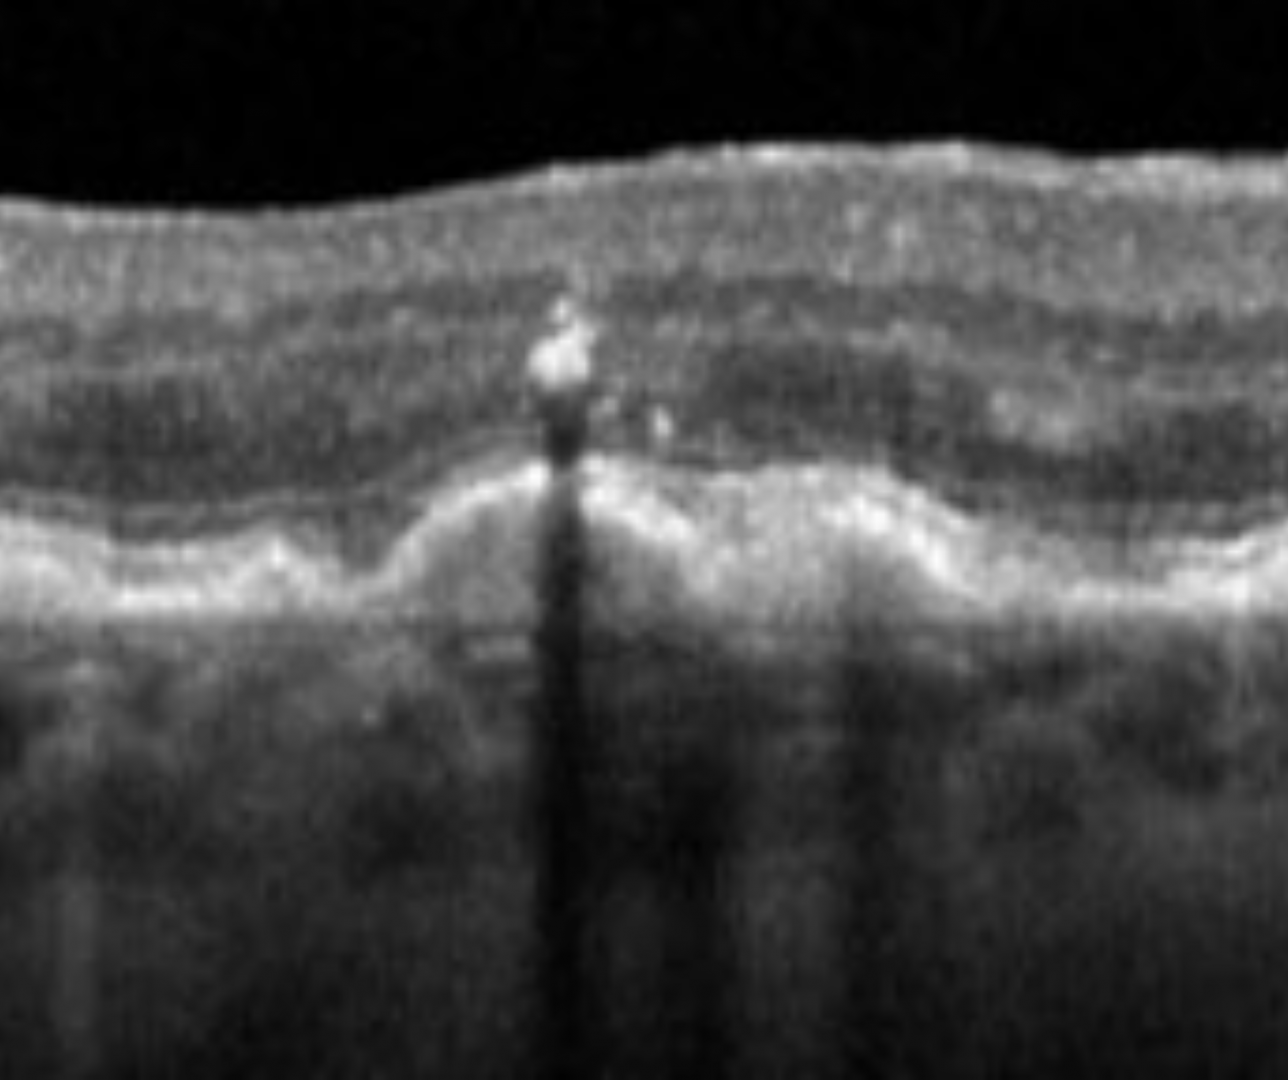

Hyper-reflective foci

Hyper-reflective foci appear as a dot-like intraretinal hyper-reflective lesion at the apex of drusen. They typically correspond to pigmentary abnormalities on funduscopic examination. Its presence is associated with a 5-fold increased risk of progression to geographic atrophy at 2 years.